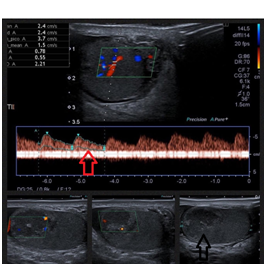

A 33 year-old male was admitted to the emergency department with a 5 -day complaint of left testicular pain, without other symptoms. At physical exam the left testis was in normal anatomic position and location, the upper pole was tender and mildly swollen with no palpable mass, past medical history was unremarkable, he denied testicular trauma or risky conducts for sexually transmitted disease. Complete blood cell count, creatinine, urinalysis were within normal range; Color Doppler ultrasound revealed a hypoechoic heterogeneous mass with a volume of 2,9 cc and preserved flow, in the upper pole of the left testis, the remaining testis exhibited normal echogenicity and vascularity (Figure 1). Tumor markers (Lactate dehydrogenase 230 U/L, β-HCG 0,10 mlu/mL, Alpha-fetoprotein 2,20 ng/ml) were negative, Abdomen CT and chest X rays did not show metastasis. Our assessment pointed to testicular neoplasia, seminoma. We scheduled the patient for radical orchiectomy; it was carried out without complications.

Figure 1 Hypoechoic heterogeneous mass located in the upper pole of the left testis of 17 x 17 x 17 mm, (L x W x H) with a volume of 2,9 cc. Black Arrow pointed to hypoechoic área on the upper pole. Color doppler US showed preserved flow within the mass, the remaining testis exhibited normal echogenicity and vascularity. Red Arrow shows preserved peak systolic velocity within the hypoechoic área of the upper pole of the left testis.